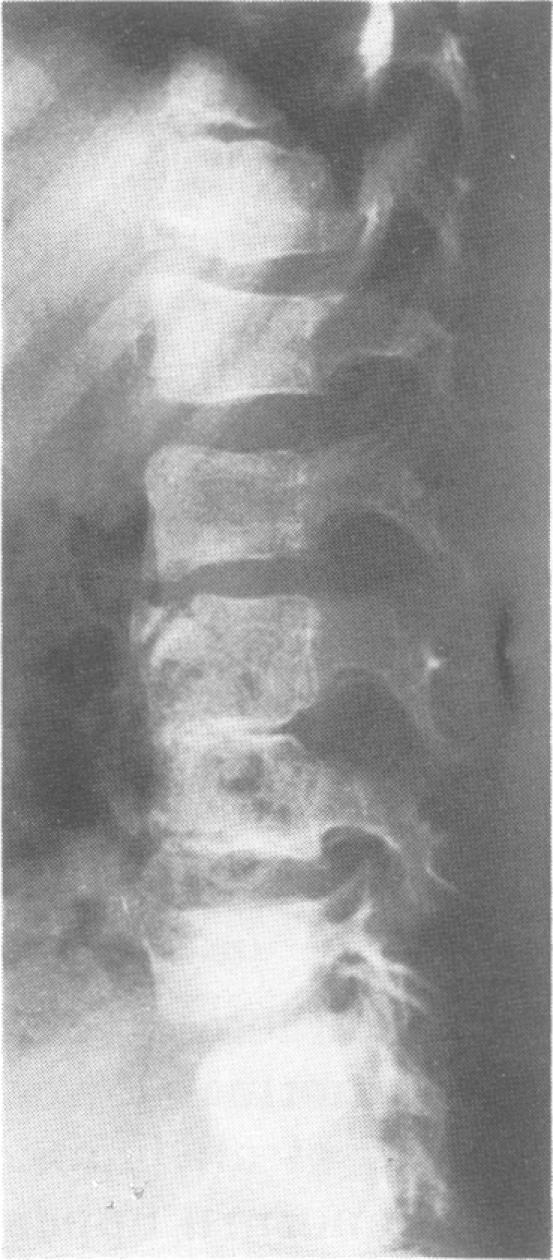

Recognition of thalidomide defects.

J Med Genet. 1992 Oct;29(10):716-23. doi: 10.1136/jmg.29.10.716.